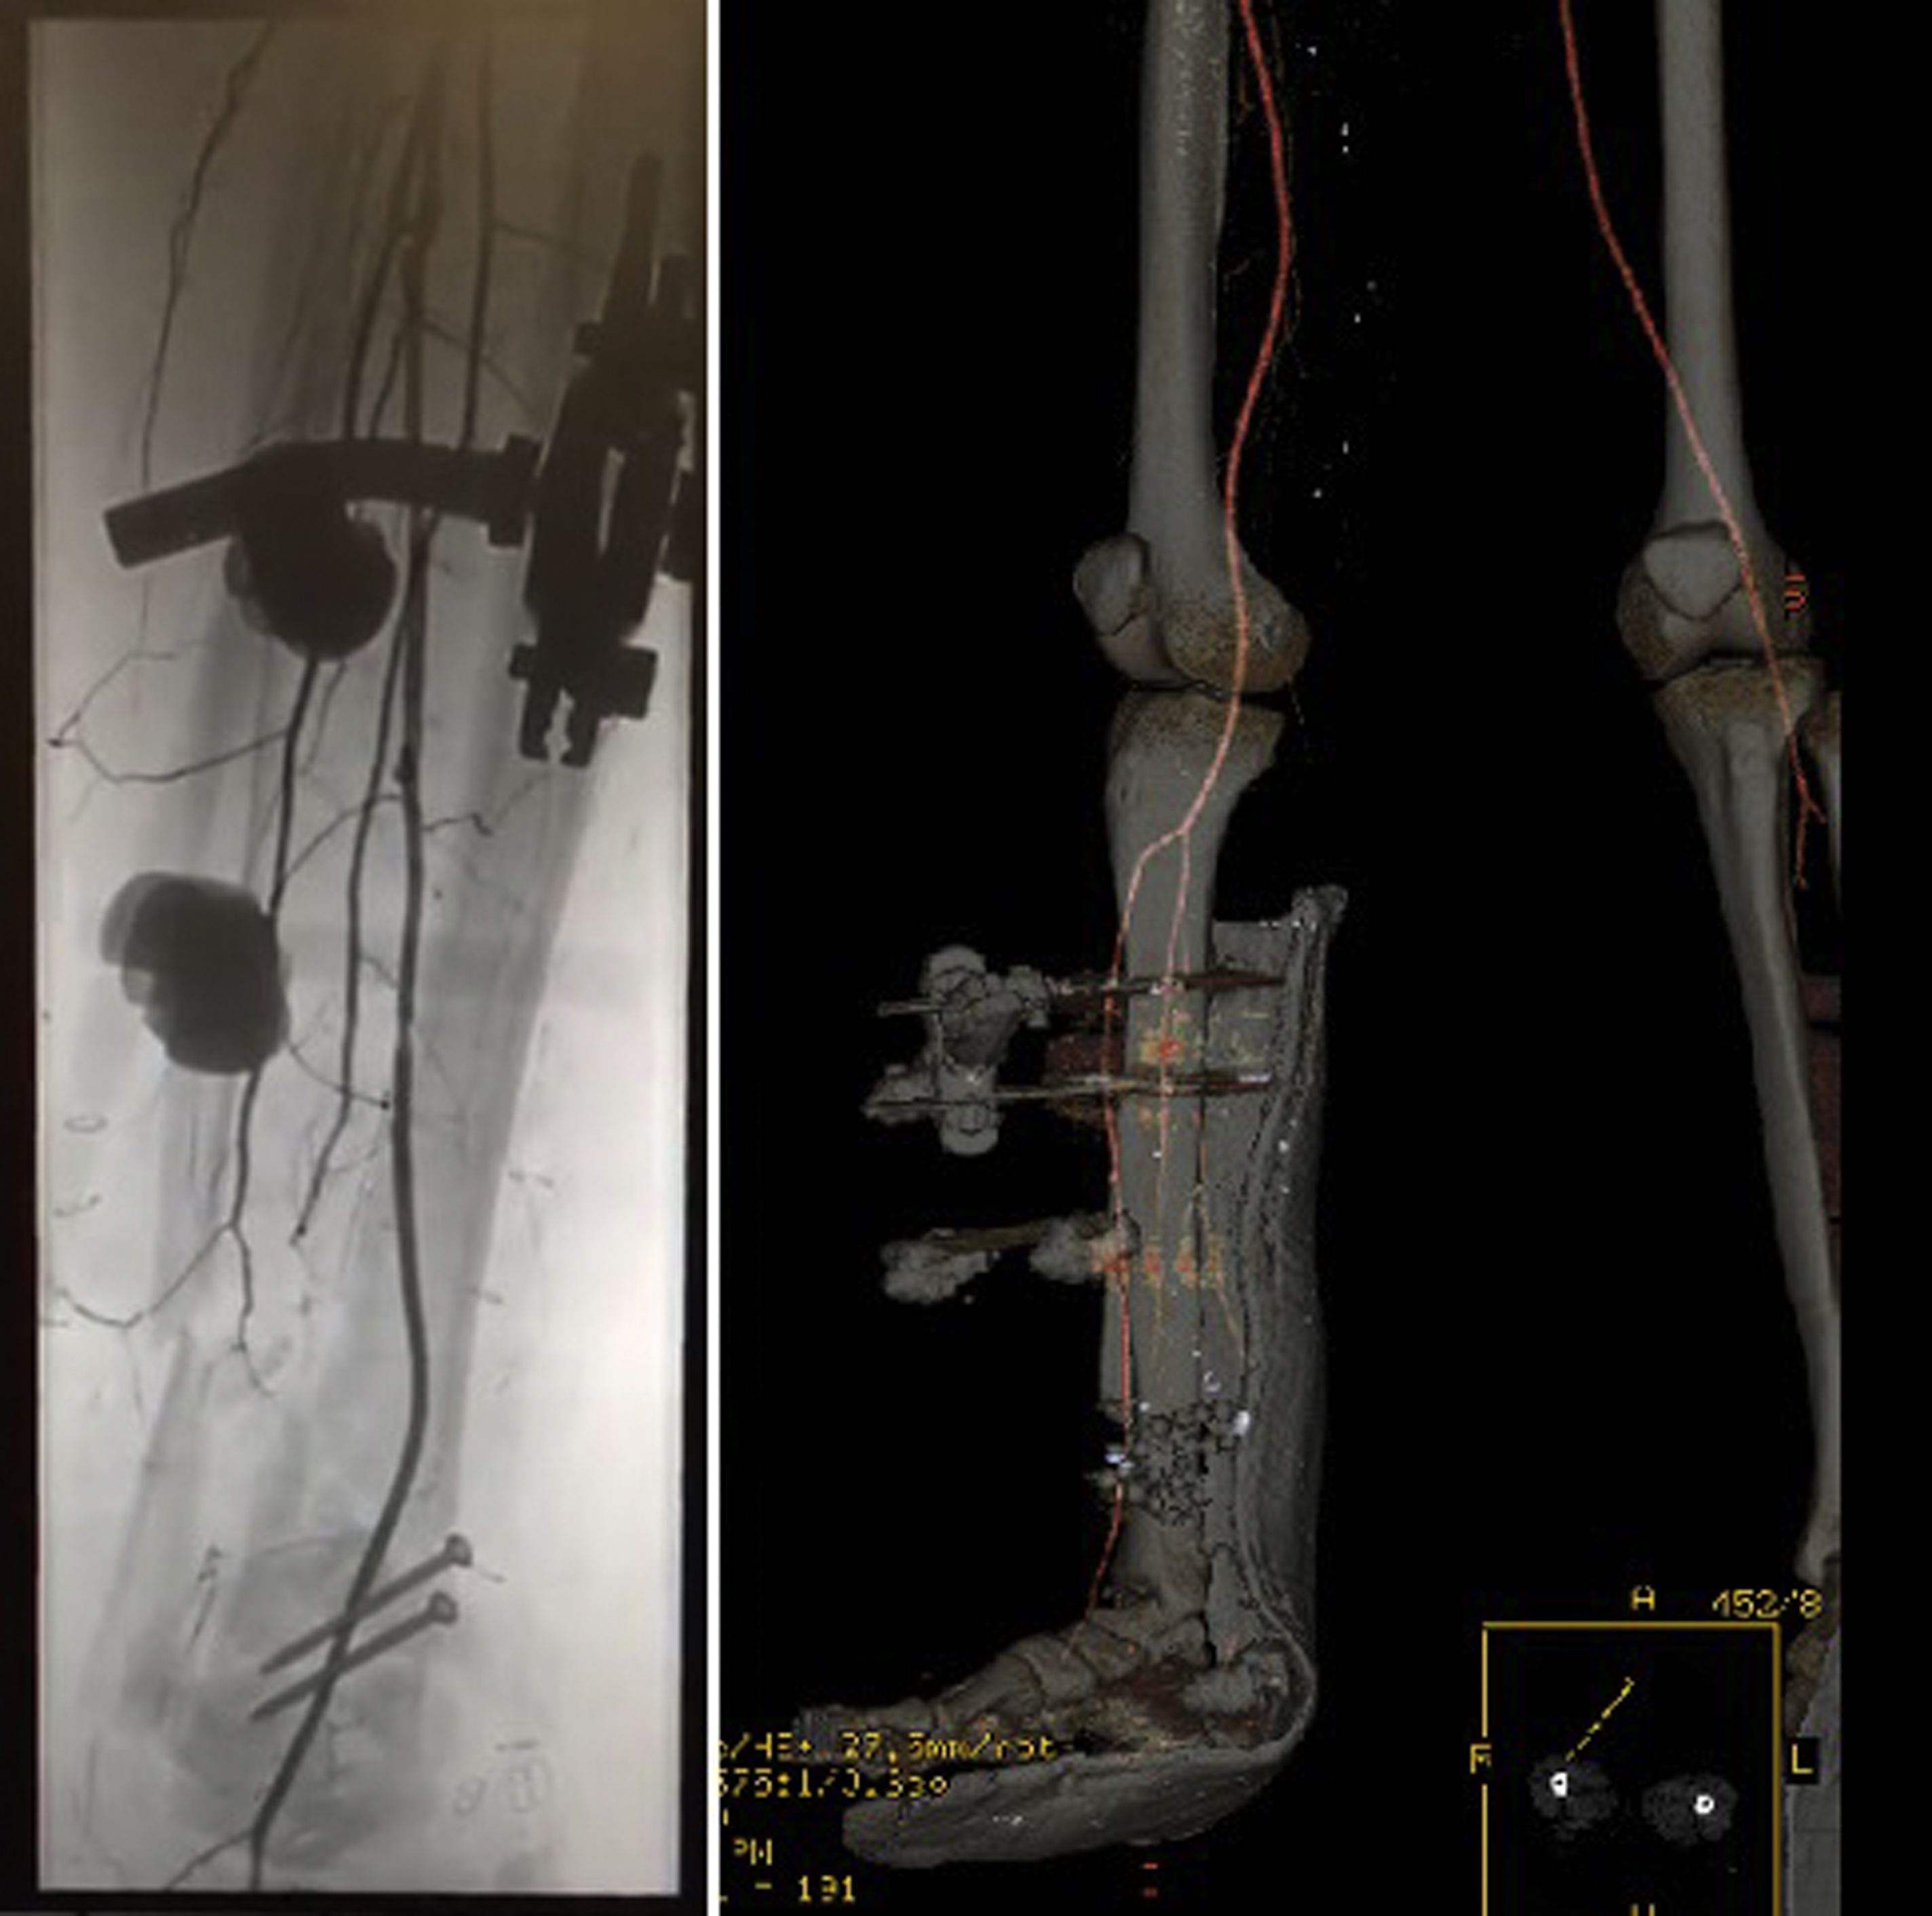

Gustilo IIIC injuries are often the result of high-energy trauma, so the initial evaluation based on advanced trauma life support (ATLS) is essential to ensure patient stability and address any immediately life-threatening injuries. Once the patient is deemed adequately stable, clinical examination of the affected limb including documentation of the pulse examination is crucial. Fig. 1 demonstrates those findings seen in a typical Gustilo IIIC injury with significant bony, soft tissue, and vascular injury.

Some debate in the literature exist as to the role of computed tomography (CT) angiograms in this patient population, but many investigators advocate for inclusion of this study in the evaluation if any of the following are present :

In addition, CT angiography represents a less expensive and less invasive option than formal angiography. However, intraoperative angiography remains the gold standard for evaluation of these injuries, and an obviously dysvascular limb should be taken to the operating room emergently following initial ATLS stabilization barring any additional life-threatening injuries requiring intervention.

A 33-year-old man sustained a right lower extremity Gustilo IIIC injury following a motorcycle crash. He initially underwent revascularization of his anterior tibial artery using a reverse saphenous vein graft ( Fig. 2 ). He was also noted to have transection of his tibial nerve with a 10 cm gap, comminuted distal tibial and fibular shaft fractures, disruption of the Achilles tendon, and 30 cm by 15 cm soft tissue defect ( Fig. 3 ). After 2 debridements, in a joint procedure with orthopedic surgery he underwent open reduction and internal fixation of the right tibia, tibial nerve reconstruction with sural nerve cable grafting, Achilles tendon reconstruction with vascularized tensor fascia lata and iliotibial band, and soft tissue coverage with a left anterolateral thigh flap and split-thickness skin grafts ( Fig. 4 ). The anterolateral thigh flap was anastomosed end to end to the disrupted posterior tibial artery, and 2 venous anastomoses were performed using 3.0 and 2.0 venous couplers, respectively. The left thigh donor site and the lateral foot were then skin grafted to complete the reconstruction.